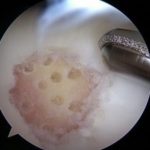

Arthroscopic surgery: One of the most commonly performed surgical procedures, includes inserting a miniature camera into the knee through a small incision. This provides a clear view of the inside of the knee. Dr. Ahmad uses tiny surgical instruments through other small incisions to trim or repair your damaged cartilage.

Articular cartilage damage in the knee (left). The cartilage damage after treatment with microfracture(right).